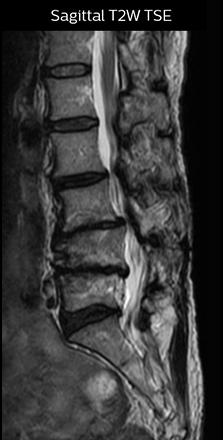

“For example, in sagittal images, when the presence of fat is observed in the intervertebral foramen, it suggests that there is a margin around the nerve. Similarly, the absence of fat indicates that the nerve is being compressed. So, we used to deduce nerve compression indirectly. With NerveVIEW, however, we can observe the condition of the nerves directly, regardless of the presence or absence of fat. We always prefer such direct observation of anatomy over having to make an inference about it.”

“Although symptoms of typical disc herniation and atypical hernia are very similar, the actual site of herniation is different. It is therefore important to characterize the nerve’s condition both inside and outside of the intervertebral foramina. “Conversely, if we see no abnormality in NerveVIEW, we can assume at least that there is no severe condition that requires surgery. Like this, it can help us avoid unnecessary surgery. NerveVIEW can have a tremendous impact in this way.”